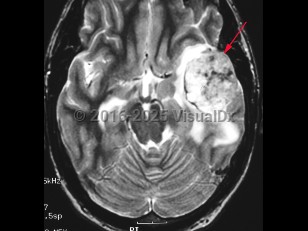

Glioblastoma multiforme

Glioblastoma multiforme is the most common primary malignant brain tumor in adults. This glial tumor is aggressive and grows quickly, invading surrounding brain tissue. Patients may present with severe persistent headaches, nausea / vomiting, seizures, memory or language impairment, or personality changes. There may also be focal deficits, such as hemiparesis, depending on the location of the tumor. Age of onset is usually 45-70 years old.

Prognosis is poor, and median survival is about 15-18 months with treatment and 3-5 months without treatment.